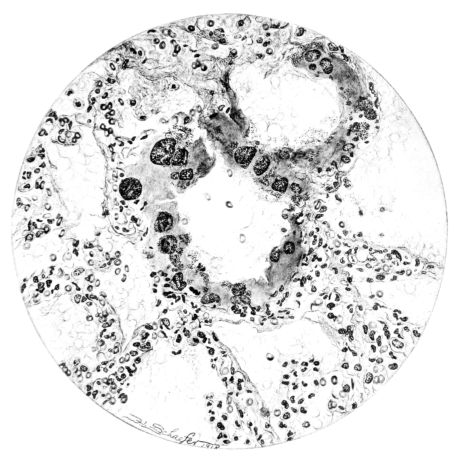

Sections from those areas of the lung where the involvement is more marked may show a histological picture not unlike that described for the aplastic stage, but, in addition, there are groups of lobules where the exudate is typically purulent and pus cells not only form the greater part of the exudate in the lumen, but are prominent in the distended vessels of the alveolar wall (Fig. XXIX). Often these leucocytes are multilobed and frequently their protoplasm is granulated with phagocytized bacteria. The bacteria are also encountered free in the alveolus along with other elements; namely, red blood cells, strands of fibrin, or precipitated albumin (Fig. XXI). The bacteria, however, are not particularly conspicuous, for generally they are either single, in pairs, or in chains; and it is only when they become clumped to form large masses, often larger than any normal tissue cell, that they attract attention. When this appearance is encountered, the alveolar wall is no longer distinct and well preserved. Although the wall may still be made out, it often stains rather homogeneously and much of the finer architecture is lost in the thrombo-necrotizing process that has been instituted (Fig. XVII).

From this intermediary stage the picture of actual abscess with mortification of bronchiolar and alveolar tissue, as well as of the exudate itself, is readily approached (25, 48, 110, 140) (Fig. XXXI). In the necrotic mass that forms the center of such a focus, the most prominent feature is the bacteria. With hematoxylin they stain intensely as black, 26irregular masses, and their prominence is accentuated by the homogeneous staining qualities (with eosin) of the dead tissue, whether lung or exudate (Fig. XXXII). These abscesses may have central cavities which represent a discharge of their contents and may indicate the position of a bronchiole (Fig. XXXI). The necrosis of the alveolar walls, focal in its distribution as previously described, suggests itself as a forerunner of the more extensive necrosis encountered at this stage.

The most extreme form of mortification is seen in the wall of a gangrenous cavity, and several layers can be distinguished there. Beginning with that portion of the lung the least involved, the lesion may be limited to congestion of the alveolar wall with a serofibrinous exudate in the lumen, but this stage passes rather rapidly into another where cellular exudate, chiefly of polymorphonuclear leucocytes, predominates. Moreover, the leucocytes form not only the bulk of the alveolar content, but also distend the vessels and accumulate in the interstitial tissue around blood vessels and lymphatics. Passing toward the center of the gangrenous cavity, the lung rapidly changes in appearance. The blue zone of leucocytic infiltration makes more conspicuous the inner area of necrosis—where nuclei no longer stain and the alveolar wall is a homogeneous pink.

Gradually this phantom architecture, spotted only here and there with disintegrating polymorphonuclear leucocytes, ends in a ragged compressed border of a shaggy pink material which has no identifying qualities (Fig. XXXV). In the inner zone of pink an occasional vessel or, at times, a bronchiole more resistant to the process remains; frequently it is accentuated by the presence of partially destroyed polymorphonuclear leucocytes at its periphery. Probably these cells invade the necrotic areas along the sheath of the bronchus or vessel and not across the dead area. The thrombotic process described in the previous stage (Fig. LII) associated with an acute arteriolitis, may be associated with these gangrenous areas as well as with infarcts (82), but more likely gangrene is preceded by the acute diffuse necrosis of the alveolar wall which occurs in the fulminating cases. Furthermore, this is suggested where a typical grey hepatization is associated with marked thinning, but not actual disappearance, of the alveolar wall. Before concluding the description of this stage of the disease, mention should be made of the granular nodules of fibrin superimposed upon the swollen pleural cells and also of the older pleural exudate, either typically fibrinopurulent or more homogeneous with broken nuclear fragments (Fig. XXXVIII).